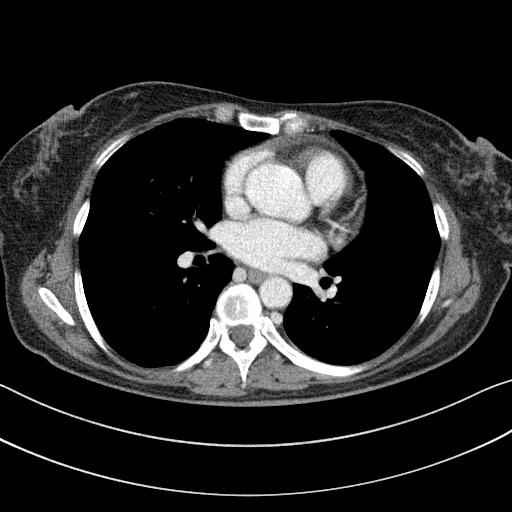

Generated VENOUS CT scan (A→B translation)

Full window (WL 1023.5, WW 4095 β†’ Low βˆ’1024, High +3071)

Actual HU range: [-1024.0, 1512.9]